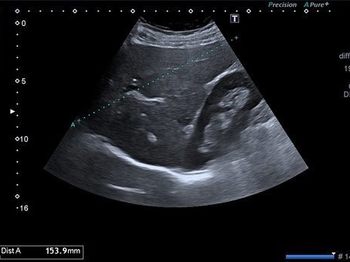

Şekilde inememiş testisin oransal olarak hangi anatomik bölgelerde yerleşmiş olabileceğini gösteren grafik görülüyor.